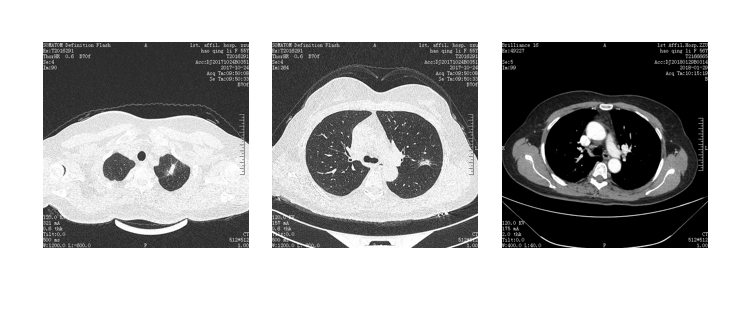

患者 女 61岁 无吸烟史

2018-06出现咳嗽,刺激性干咳,偶有痰中带血,伴胸闷、心悸,在新县人民医院行胸部CT示:左肺舌叶周围性肺癌,建议结合病理学检查。予以抗感染治疗后出院,期间症状反复出现;

2018-10出现胸闷、胸痛症状,继续在当地医院治疗(具体不详),症状未见减轻。

2018-11-22来我院行胸腹部CT示:

1、左侧胸腔占位,考虑恶性,胸膜间皮瘤侵及左肺及左主支气管可能性大,建议结合病理。

2、右肺下叶炎症。

3、左侧胸腔大量积液。

4、腹部CT未见异常

双侧胸廓不对称,纵隔右侧移位,左侧胸腔一巨大团块状高密度影,大小约13.8cm×9.4cm×16.6cm(前后径×左右径×上下径),余肺组织呈受压改变,左侧胸膜呈结节样增厚,增强后呈轻度不均匀强化,内见相对低密度区。左主支气管内见结节样软组织密度影,呈轻度强化,余气管、支气管通畅,纵隔内未见明显肿大淋巴结,左侧胸膜腔见明显积液征象。

左肺腺癌Ⅳ期(cT4N0M1a 胸腔积液)